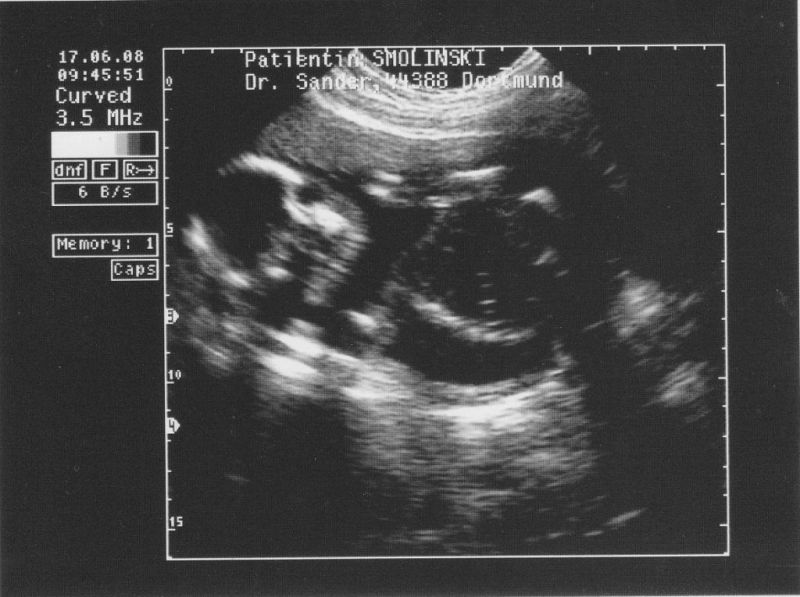

Und bald kommt noch jemand dazu....

Um genau zu sein am Donnerstag per Kaiserschnitt :]